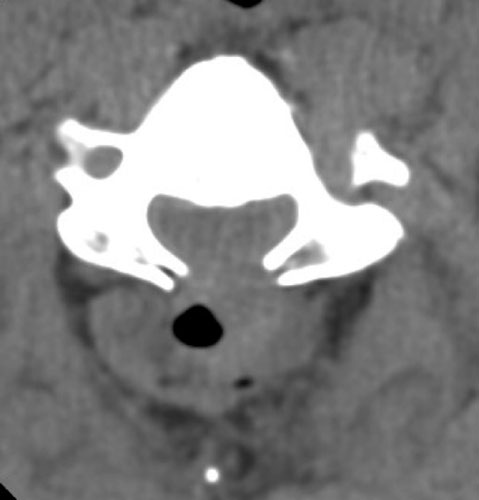

63 y.o. male with severe spinal stenosis and associate myelopathy in both hands and feet. Patient underwent laminectomy from C2-C7. 1 day after initial operation patient with severe numbness to left arm. Then, patient became unable to move either leg within 2 hours after that initial complaint. A Stat non-contrast CT was ordered.

Axial CT demonstrates laminectomy defect at the level shown. A hyperdense fluid collection with some air bubbles  is identified consistent with an epidural hematoma, extending from the C2-3 level to C7-T1 .